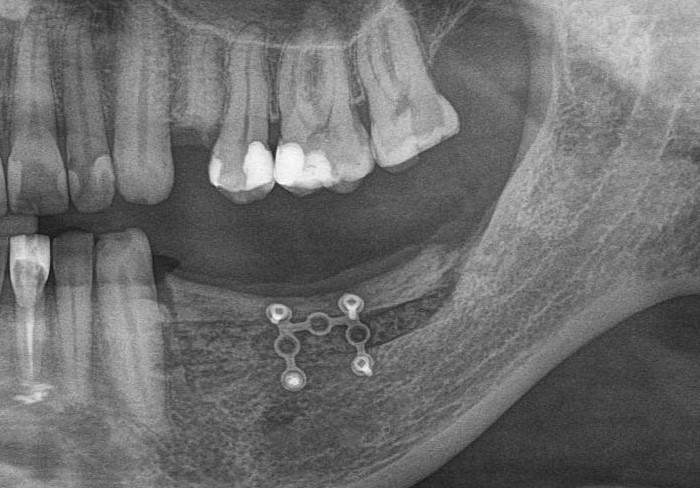

Например, в таком случае:

я бы зассал делать остеотомию предпочёл бы другой метод остеопластики

После операции мы делаем контрольные снимки. Это может быть ортопантомография:

или конусно-лучевая компьютерная томография. Как вам больше нравится.